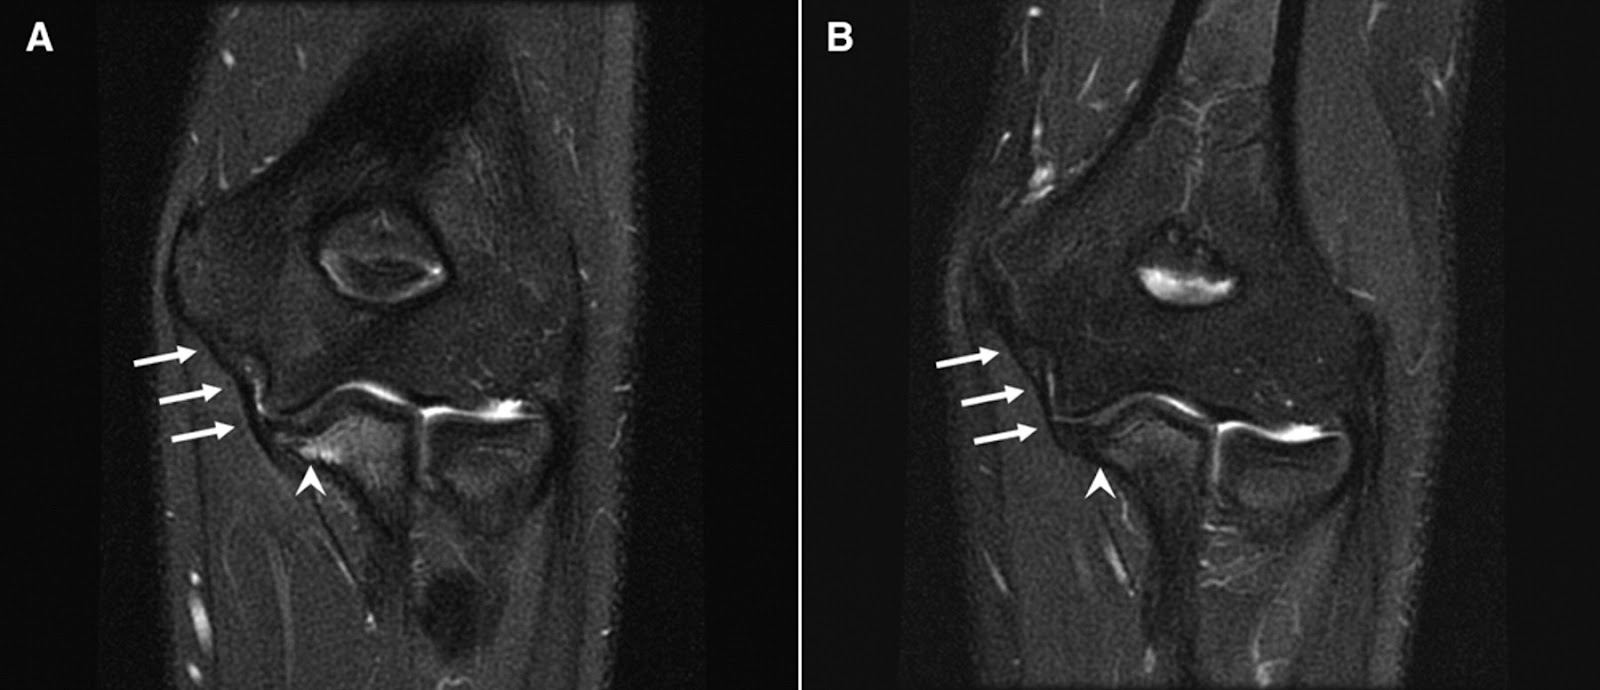

MRI of distal disruption of the ulnar collateral ligament at its... Download Scientific Diagram Mri Anatomy Ulnar Collateral Ligament When discussing ucl injury, understanding severity is important for sports medicine providers to be. The ulnar collateral ligament connects the ulnar styloid process with the triquetrum in a longitudinal orientation deep. The lateral ulnar collateral ligament (lucl) also originates on the lateral epicondyle and extends behind the radial head to attach to. Lateral (left) and posterior (right) 3d renders of. Mri Anatomy Ulnar Collateral Ligament.